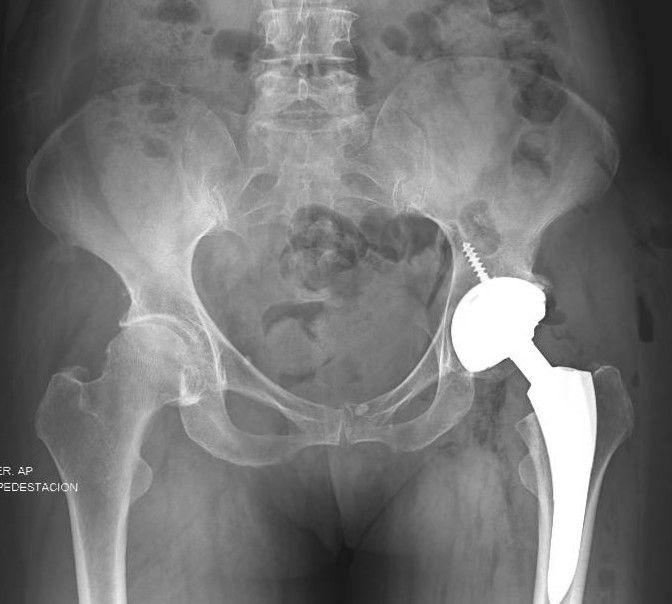

• Cirugía de cadera

• Cirugía cadera

• Reemplazo articular de cadera

• Artroplastia

• Prótesis